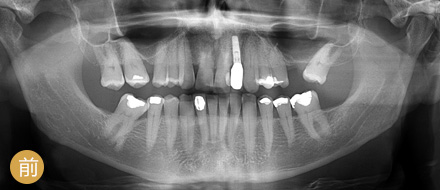

数字化精确导航种植

导航辅助种牙,创口小更舒服

• >智能导航,精确高效

• >适用症广,缺牙重生

• >避免盲种,成功率高

• >种牙精准,不伤神经